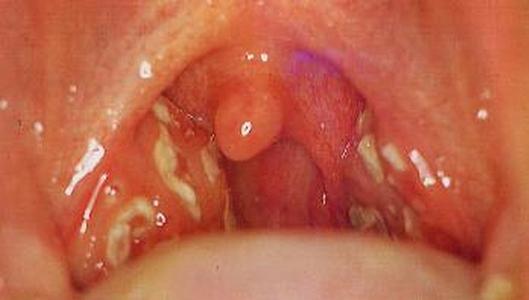

- Фолликулярная ангина. Характерным является:

- поражение фолликул, достаточно глубокое;

- явное покраснение и сильная отёчность слизистой;

- образование гнойного налёта, который невозможно снять при обработке;

- высокий риск слияния гнойничков в абсцесс.

- При гнойной ангине наблюдаются белые или желтоватые гнойнички на миндалинах.